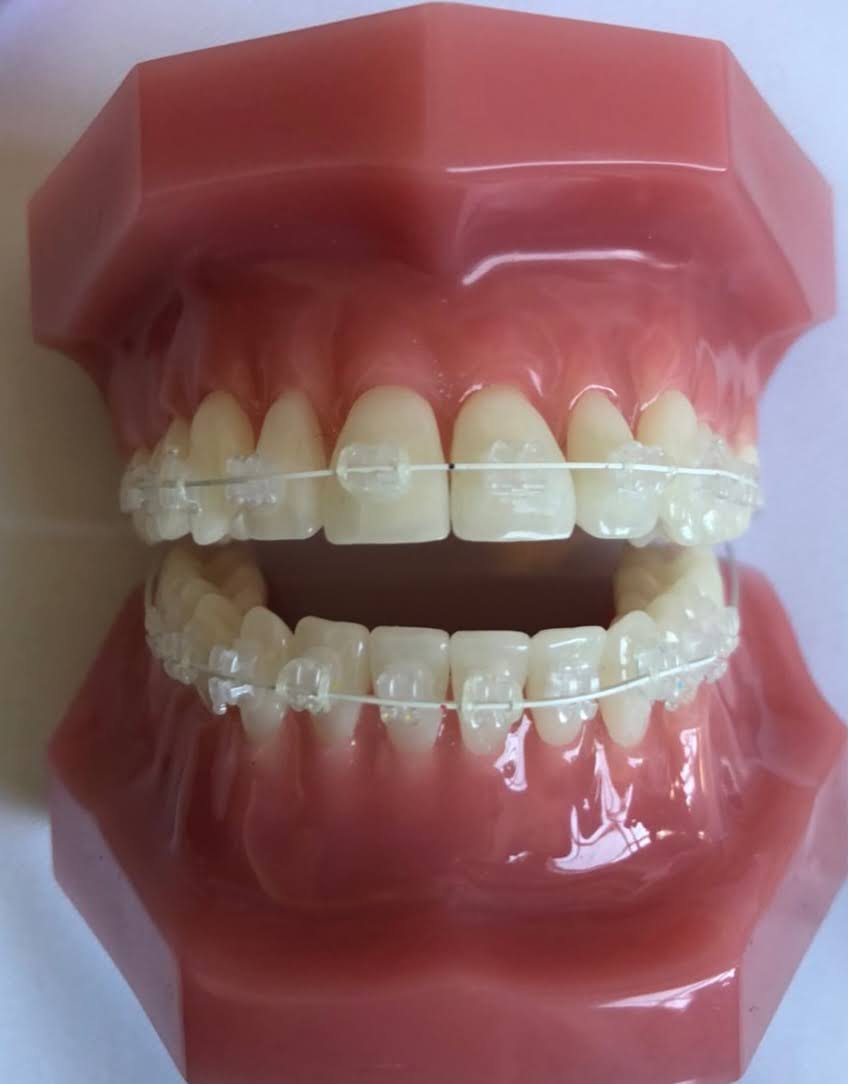

ワイヤー矯正

ねじれや上下的なズレがある中〜重度の後戻りには、ワイヤー矯正が適応します。

表側・裏側どちらも選択でき、細かい歯の動きを正確にコントロールできます。

歯を抜かない矯正治療 全体矯正から気になる部分だけもできるワイヤー矯正について